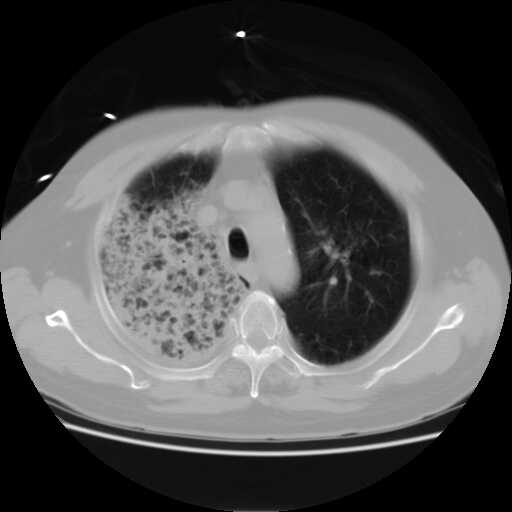

2008.8.17ct

病变从8.11-8.17明显改变,增多,以蜂窝状改变为主,类蜂窝肺,似弥漫性肺泡癌,但是病变进展太快,不符合弥漫性细支气管肺泡癌。因此考虑为特殊微生物感染,多以霉菌类常见,建议细菌微生物学检查。

疑点二:影象表现怪异,大片阴影内见多发筛孔征,如何解释.

结合临床慢支炎肺气肿,肺心病病史,三次胸片观察可见病情发展变化迅速,病情凶险,考虑多重感染伴ards.